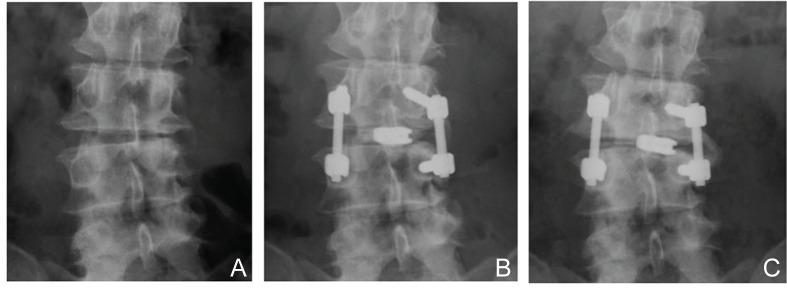

Transforaminal lumbar interbody fusion (TLIF) is widely accepted for the treatment of lumbar arthrodesis. However, the exact characteristics of TLIF depend on the number, location, shape, or materials of the interbody implants, and the type of posterior instrument. Clinical and biomechanical characteristics of each TLIF procedure are still unclear. The present study investigated the clinical and radiological improvements after single level asymmetrical TLIF, in which a single box-shaped spacer was obliquely inserted into the intervertebral space, for lumbar degenerative spondylolisthesis in patients with or without local coronal imbalance (LCI) at the operated level. The clinical records of 60 patients who underwent single level asymmetrical TLIF augmented with the pedicle screw fixation system from January 2005 to January 2011, were retrospectively reviewed. The patients were divided into the LCI group (n = 19) and non-LCI group (n = 41), based on segmental lateral translation or disc wedging at the operated site. Clinical recovery was significantly good in both groups at 2 years after surgery, but improvement of low back pain was significantly worse in the LCI group. Radiological examination revealed that the mean lumbar scoliotic angle was significantly worse in the LCI group postoperatively. Preoperative greater scoliotic angle and coronal off balance of the lumbar spine were related to unfavorable radiological outcomes. The present study showed that single level asymmetrical TLIF is an acceptable method for achieving good clinical and radiological outcomes for patients with symptomatic degenerative spondylolisthesis, however, the clinical benefits and realignment are limited if the patient has LCI at the operated site with greater scoliotic angle or coronal off balance of the lumbar spine.